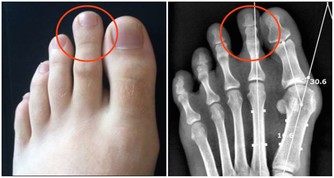

2、腳後跟痛

早上醒來腳落地感覺腳後跟痛,彷若針扎一般疼,稍微起身行走片刻緩解,但繼續運動或長久站立疼痛感又會襲來,此時應當提高警惕了,如果腳後跟並沒有紅腫且皮膚無破損,需要懷疑是足底筋膜炎的問題。